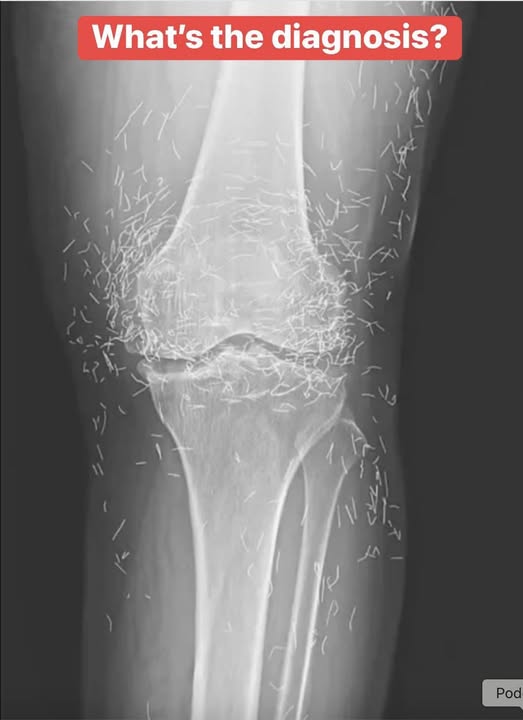

Doctors Shocked by What They Found Hidden Inside a Woman’s Knee X-Ray

What began as a routine hospital visit for knee pain turned into a shocking medical mystery. A 65-year-old woman in South Korea expected a simple arthritis diagnosis—but when her X-ray appeared, doctors were stunned. Her knee joint was filled with dozens of tiny gold needles, leaving everyone wondering how they got there and why they hadn’t been discovered sooner.

However, instead of using temporary needles, her acupuncturist had implanted fine gold ones beneath her skin permanently, believing they would release healing energy over time. This unusual practice was meant to provide continuous pain relief without repeated sessions.